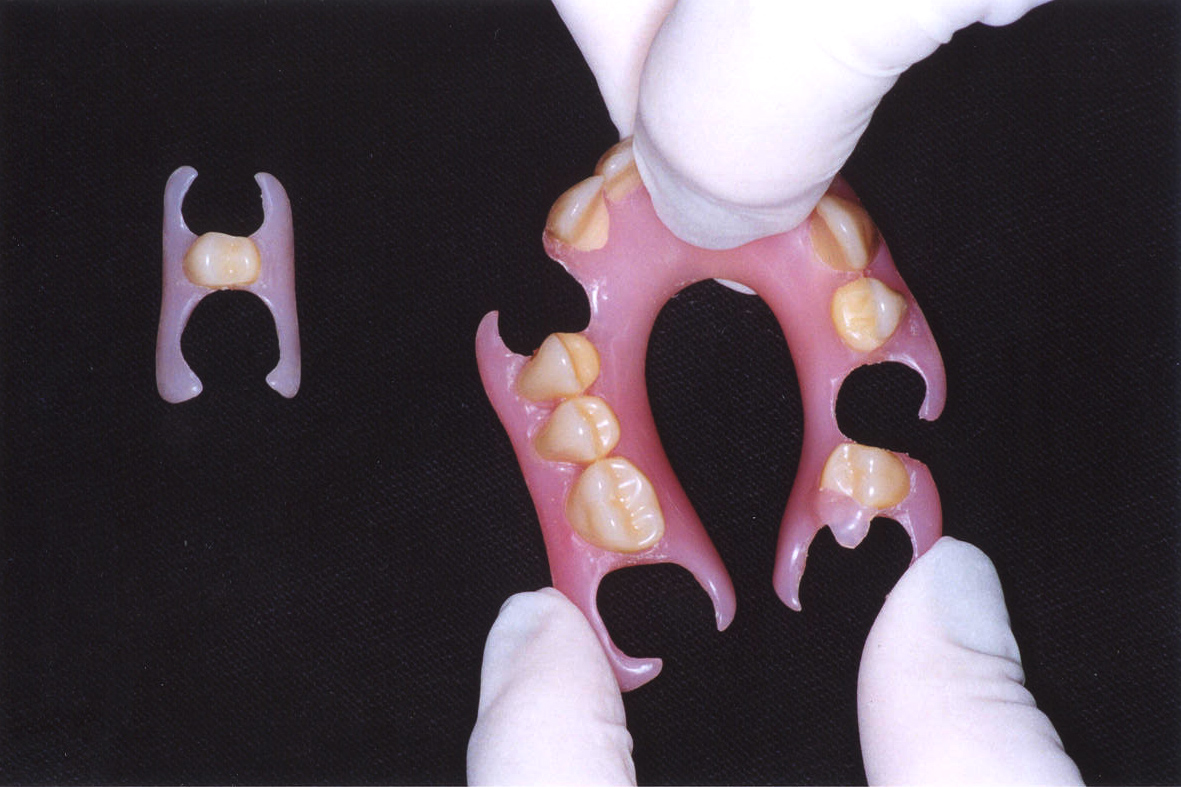

Próteses Flexíveis Termoplásticas

SLIDE PRINCIPAL(COM POLIMEROS)Saude_Bucal_Ctba-CPODPALESTRA 2009 – cópiaSLIDE TONALIDADESHERMÍNIO HOMMETOSLIDE INJETORA TERMOPLÁSTICACURSO…